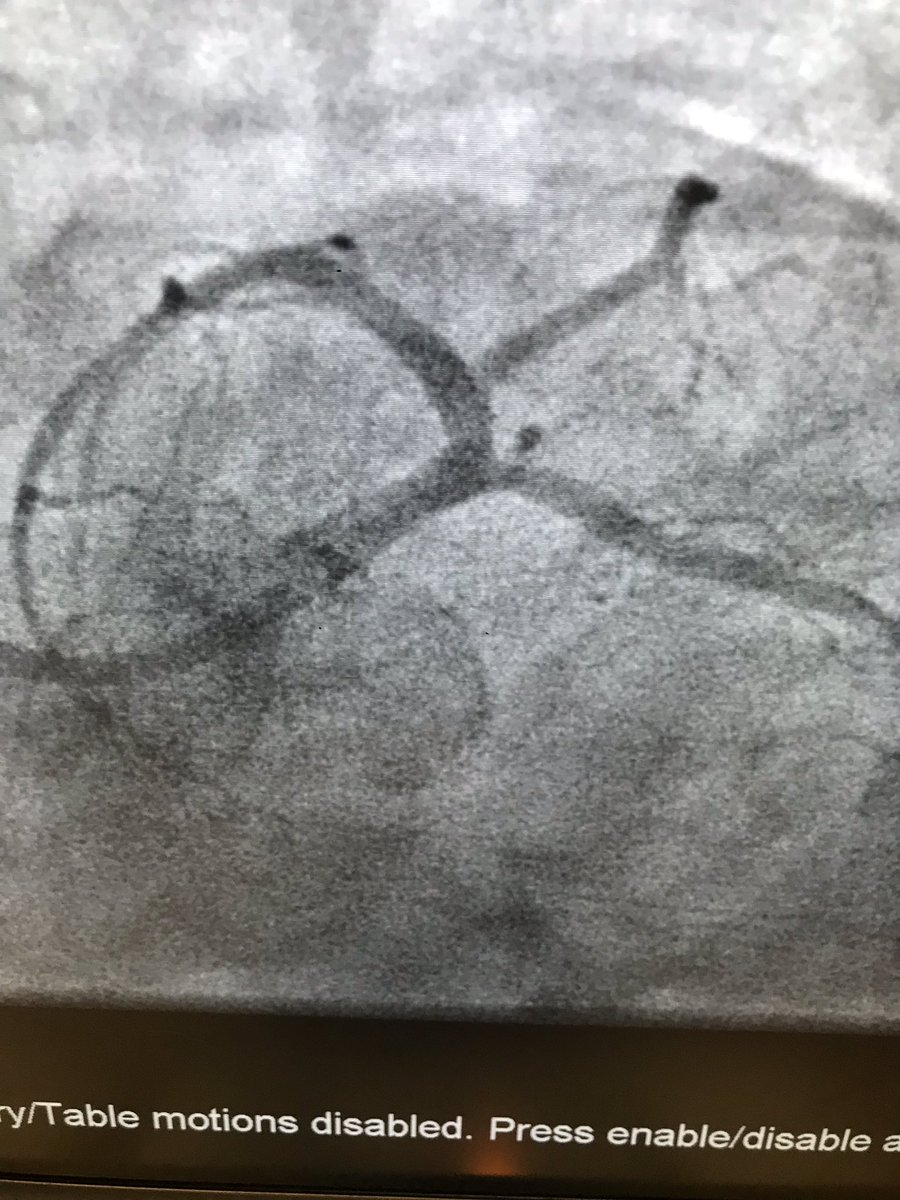

#safefemoral #protectedpci 62 m anterior stemi ivus guided into left main . Ef 50% at d/c

istentem's tweet image. #safefemoral #protectedpci 62 m anterior stemi ivus guided into left main . Ef 50% at d/c